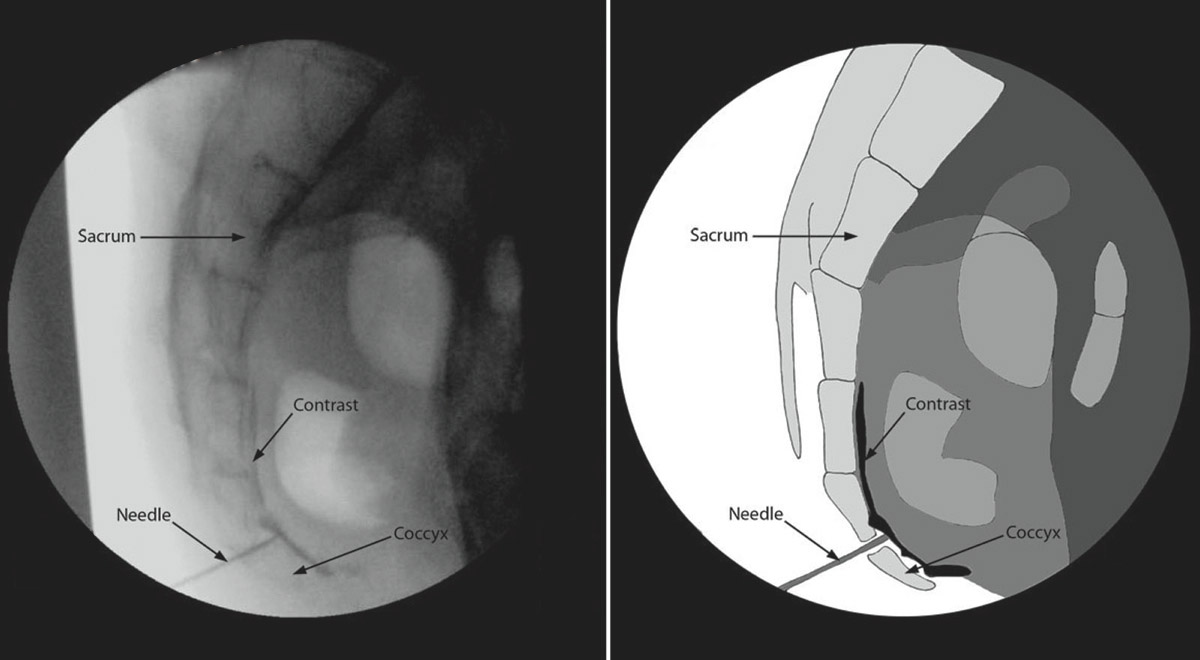

Ganglion Impar Block